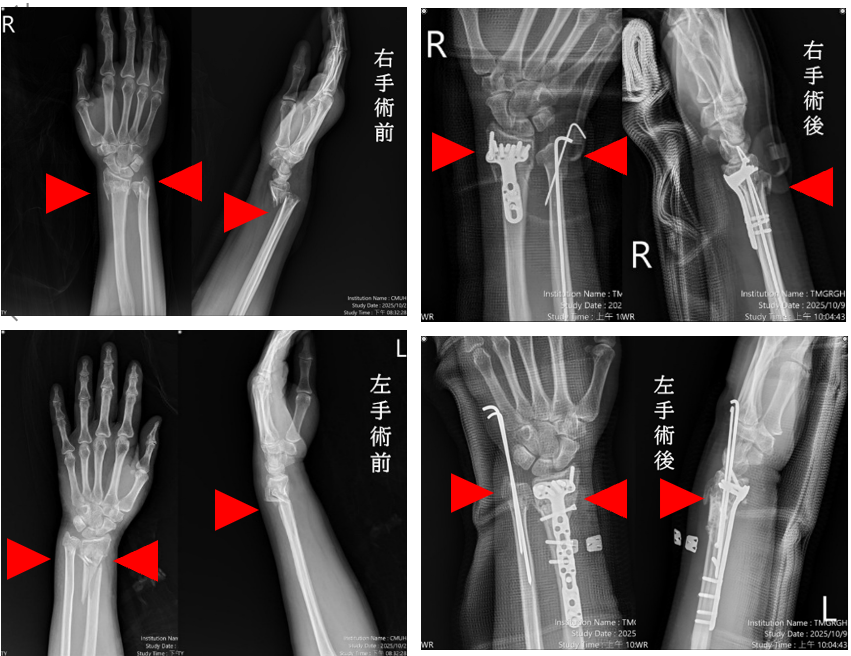

本院「機器人微創脊椎中心」創醫療新紀錄!一名57歲婦人因交通事故導致雙手多處骨折與脫位,經本院急診救治,診斷為粉碎性複雜性骨折,本院啟動「多主治醫師協同手術機制」,由「機器人微創脊椎中心」骨科部蘇伯翰、江晟弘、毛睿廷三位主治醫師同步進行左右手微創手術,僅一小時即完成四處骨折修復,術後三日順利出院。此創新機制將傳統五小時的手術時間縮短為一小時,大幅減少疼痛與麻醉副作用,並降低醫療人力負擔。

蘇伯翰醫師指出,該名傷患送至本院急診後,即時進行復位與石膏固定,並於24小時內安排開刀,採用「多主治協同手術模式」,由三位主治醫師同時操作左右手四處骨折微創手術,縮短手術時間至約一小時,協同分工可加快病患恢復速度,並提升安全性。患者傷口小、出血少,隔天即可開始復健,三天後平安出院,恢復良好。